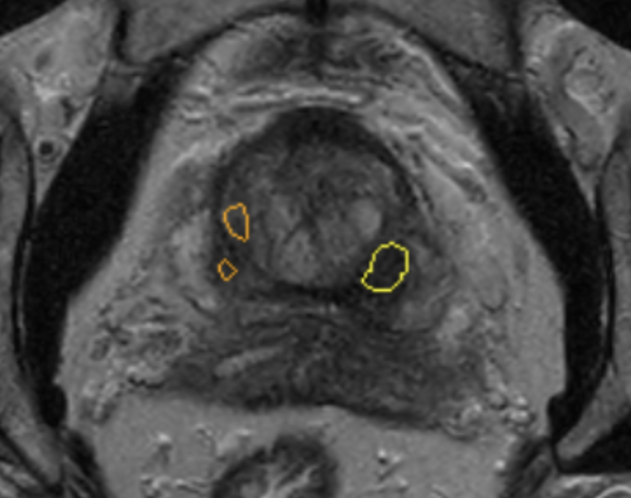

Quibim’s flagship product, QP-Prostate®, is the result of years of research in computer vision. By using biopsy results as ground truth for training and validation, QP-Prostate® identifies and highlights suspicious lesions on prostate, enhancing radiologists’ accuracy and efficiency.

The software provides radiologists with a visual representation of the lesion, and a degree of certainty on the software’s prediction when determining if a lesion could be csPCa.